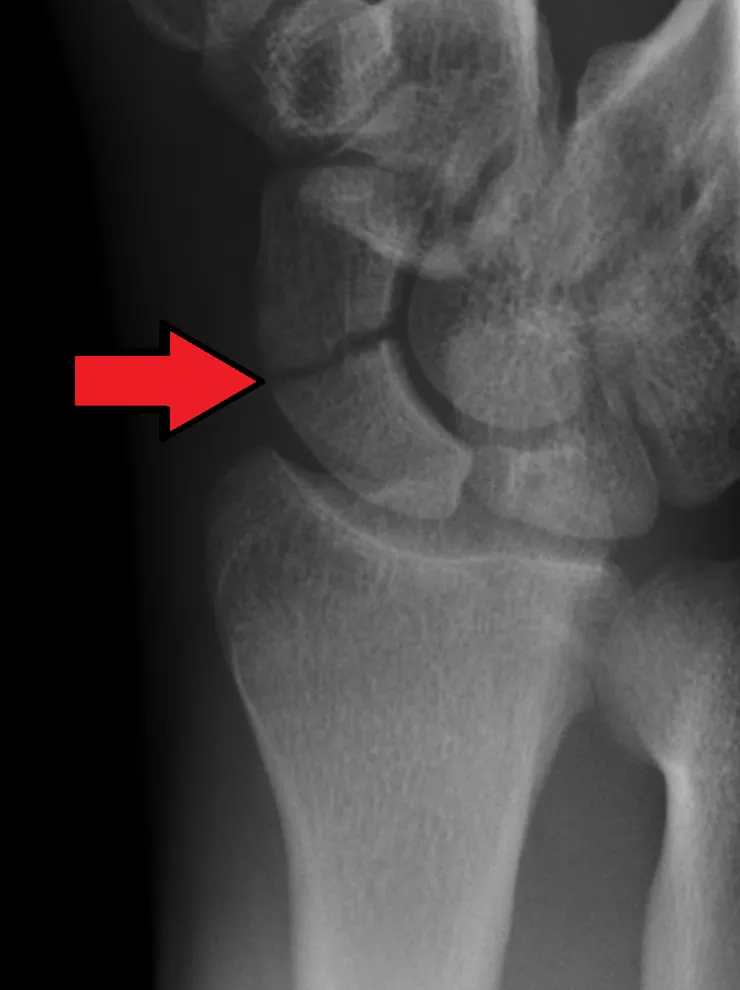

舟狀骨骨折( scaphoid fracture )

這也是手腕傷害最容易傷到的地方,而也因為是常動用到之地方,所以在癒合及復原也會比較久。久而久之會導致動力學跑掉、ROM、力量下降及腕關節退化

舟狀骨骨折有時候難以診斷。若是初期X光未發現骨折,可以以石膏,或是護具固定兩週。之後再每兩週檢查一次至確定無骨折且改善

若疼痛遲遲無改善,可做骨骼掃描( Bone scan )或是磁核共振( MRI study )來查出隱藏的骨折

*舟狀骨骨折常常被忽略,而且後遺症很嚴重,當手腕持續疼痛就必須注意舟狀骨是否有骨折